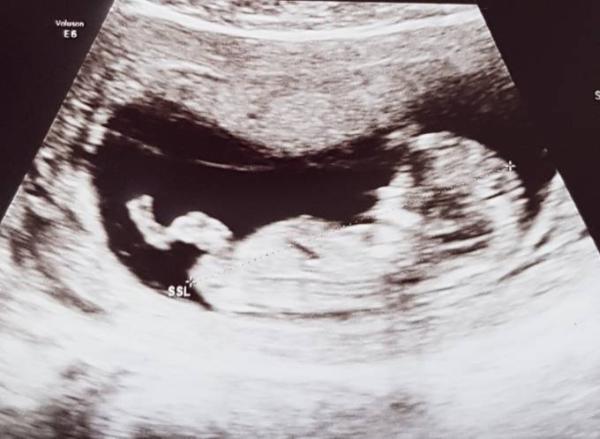

Oh mein Gott Das war das süßeste was ich je gesehen hab! Da ist dieser kleine Fratz in meinem Bauch rumgeturnt, als wolle er hochleistungssportler werden! Nackenfalte ist tipitopi bei 1,0 Alle Herzkammern sind aktiv, der Rücken geschlossen, eine Nase hats auch :D Der Doc. ist super zu Frieden! Und ich auch! Wahnsinn! Laut U-schall sind wir auch schon eine Woche weiter- bei 12+1 statt 11+1. Und nun, die Fragen aller Fragen... Geschlechtstechnisch- könnt ihr da iiiiirgendwas erkennen? ich bin so verliebt! Am liebsten hätte ich dem kleinen Fratz noch Stunden bei seinen Turnübungen zugeschaut.

Bild zu Nackenfaltenmessung bestanden! - Forum für April - Mamis

Was meint ihr? Kann man da überhaupt was sehen?

Bild zu